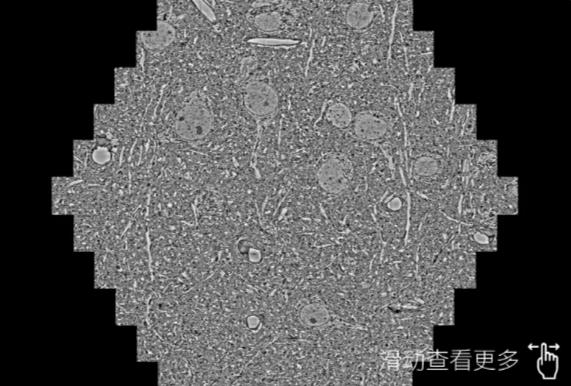

鼠脑切片。左图使用河源蔡司河源扫描电镜MultiSEM706对165μmx143pm面积区域成像,耗时仅需1.5秒。右图为鼠脑切片中30μm区域放大效果。样品由芝加哥大学B.Kasthuri提供。

使用蔡司高速河源扫描电镜MultiSEM对1mm²人脑皮层组织进行高分辨成像,并对其中的各种细胞结构进行三维重构分析。左图展示了2x3mm²组织平面中锥体神经元的三维重构效果。右图显示了局部体积神经元三维重构。图像由哈佛大学chtman实验室提供,渲染图由D. Berger 制作。